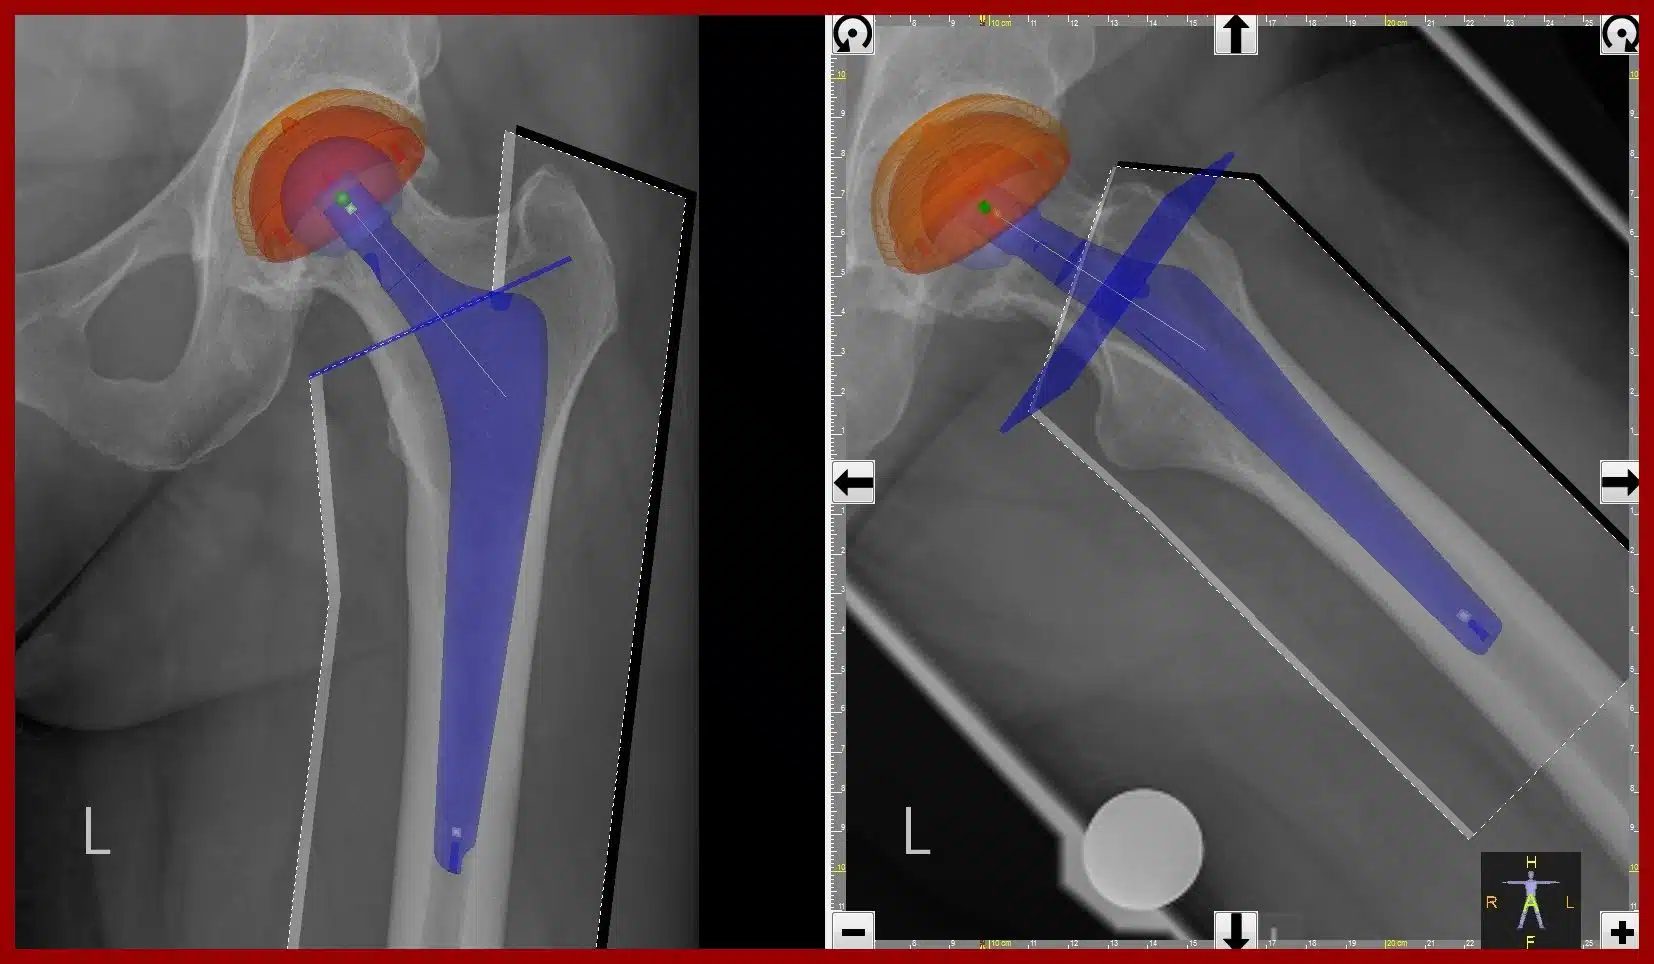

2.Total Hip Replacement

In a total hip replacement, part of the thigh bone (femur) including the ball (head of femur) is removed and a new, smaller artificial ball is fixed into the rest of the thigh bone. The surface of the existing socket in the pelvis (the acetabulum) is roughened to accept a new socket component that will join up (articulate) with the new ball component. Many artificial joint components are fixed into the bone with acrylic cement. However, it’s becoming more common, especially in younger, more active patients, for one part (usually the socket) or both parts to be inserted without cement. If cement isn’t used, the surfaces of the implants are roughened or specially treated to encourage bone to grow onto them. Bone is a living substance and, as long as it’s strong and healthy, it’ll continue to renew itself over time and provide a long-lasting bond. Where only one part is fixed with cement, it’s known as a hybrid hip replacement. The replacement parts can be plastic (polyethylene), metal or ceramic and are used in different combinations:

- Metal-on-plastic (a metal ball with a plastic socket) is the most widely used combination.

- Ceramic-on-plastic (a ceramic ball with a plastic socket) or ceramic-on-ceramic (where both parts are ceramic) are often used in younger, more active patients.

- Metal-on-metal (a metal ball with a metal socket) is very occasionally used in younger, more active patients